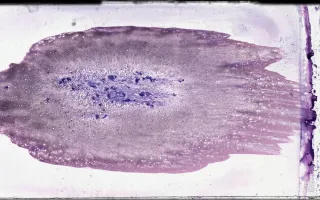

Morphologically, dense infiltrates of mast cells(>=15 mast cells in aggregates) are detected in a section of bone marrow and >25% of the mast cells in the infiltrate are spindle-shaped or have atypical morphology. In this case, the patient’s manifestations are relatively limited, consistent with an indolent subvariant of systemic mastocytosis.

In this case the peripheral blood smear and bone marrow aspiration smear findings are unremarkable. The bone marrow biopsy shows aggregates of atypical mast cells. There are a few well-circumscribed non-paratrabecular lymphoid aggregates composed of a mixture of B and T-lymphocytes. Foci of moderate fibrosis are seen with a reticulin stain and they are associated with the mast cell and lymphoid aggregates. CD117 highlights scattered spindled mast cells which are also present in aggregates. The mast cells are positive for CD25 and mast cell tryptase and negative for CD2.

This slide shows bone marrow aspiration smear which is unremarkable. See Related Content for H&E, reticulin, CD25, CD117, tryptase, CD2, CD3 and CD20 stains of the bone marrow biopsy. Peripheral blood smear (unremarkable) is also shown.